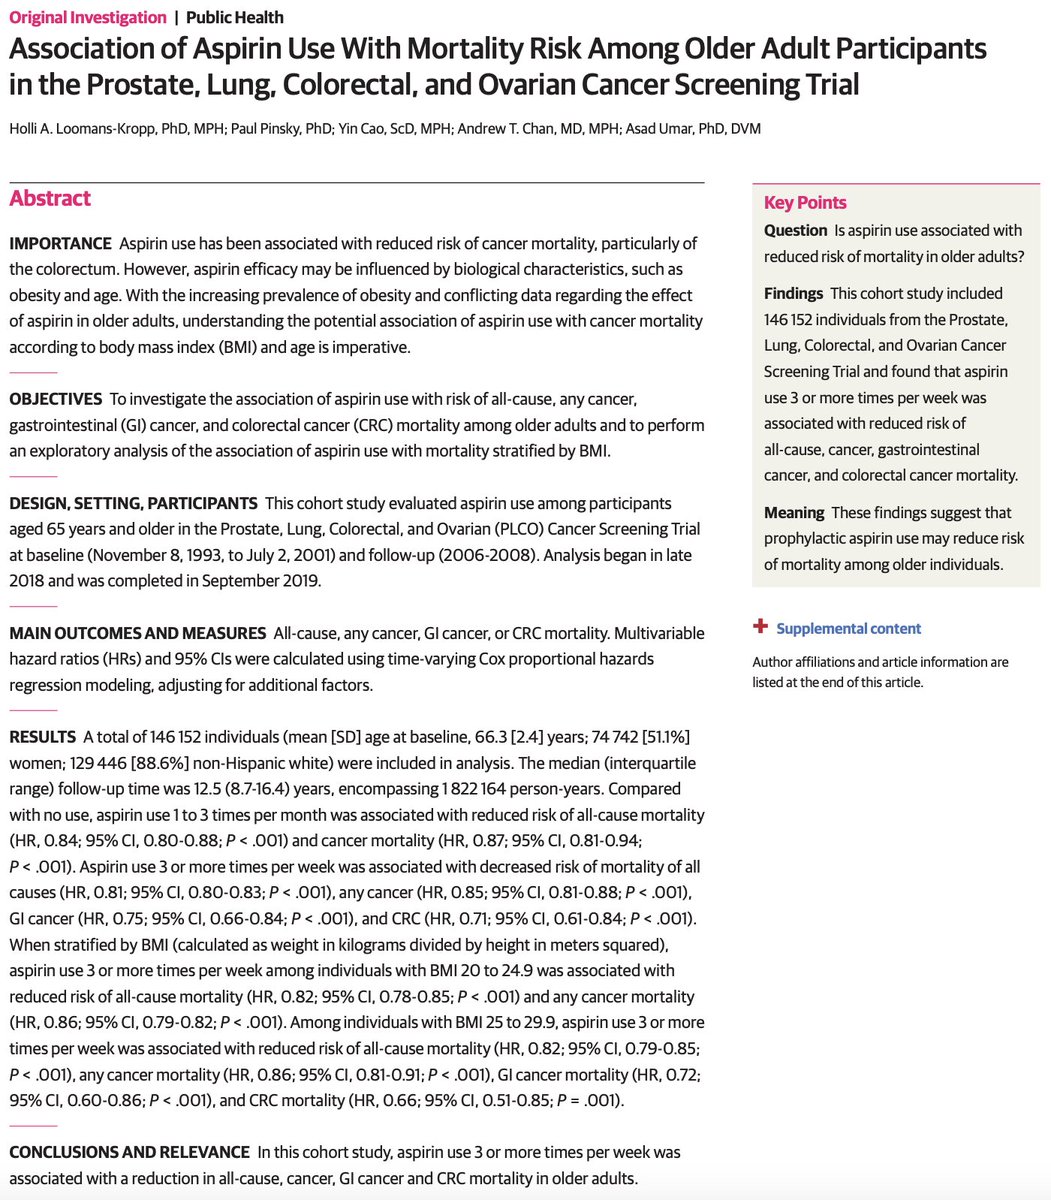

Aspirin’s primary metabolite IMPROVES insulin resistance, a common underlying factor behind almost EVERY disease you can think of.

◦ IMPROVES glucose metabolism

◦ REDUCES blood sugar

◦ REDUCES C peptide (insulin)

◦ Improves inflammatory markers

◦ IMPROVES glucose metabolism

◦ REDUCES blood sugar

◦ REDUCES C peptide (insulin)

◦ Improves inflammatory markers

Aspirin’s ability to treat diabetes dates back over 100 years, with doctors in the late 1800s and early 1900s showing that aspirin metabolites could completely halt the excretion of sugar into the urine.